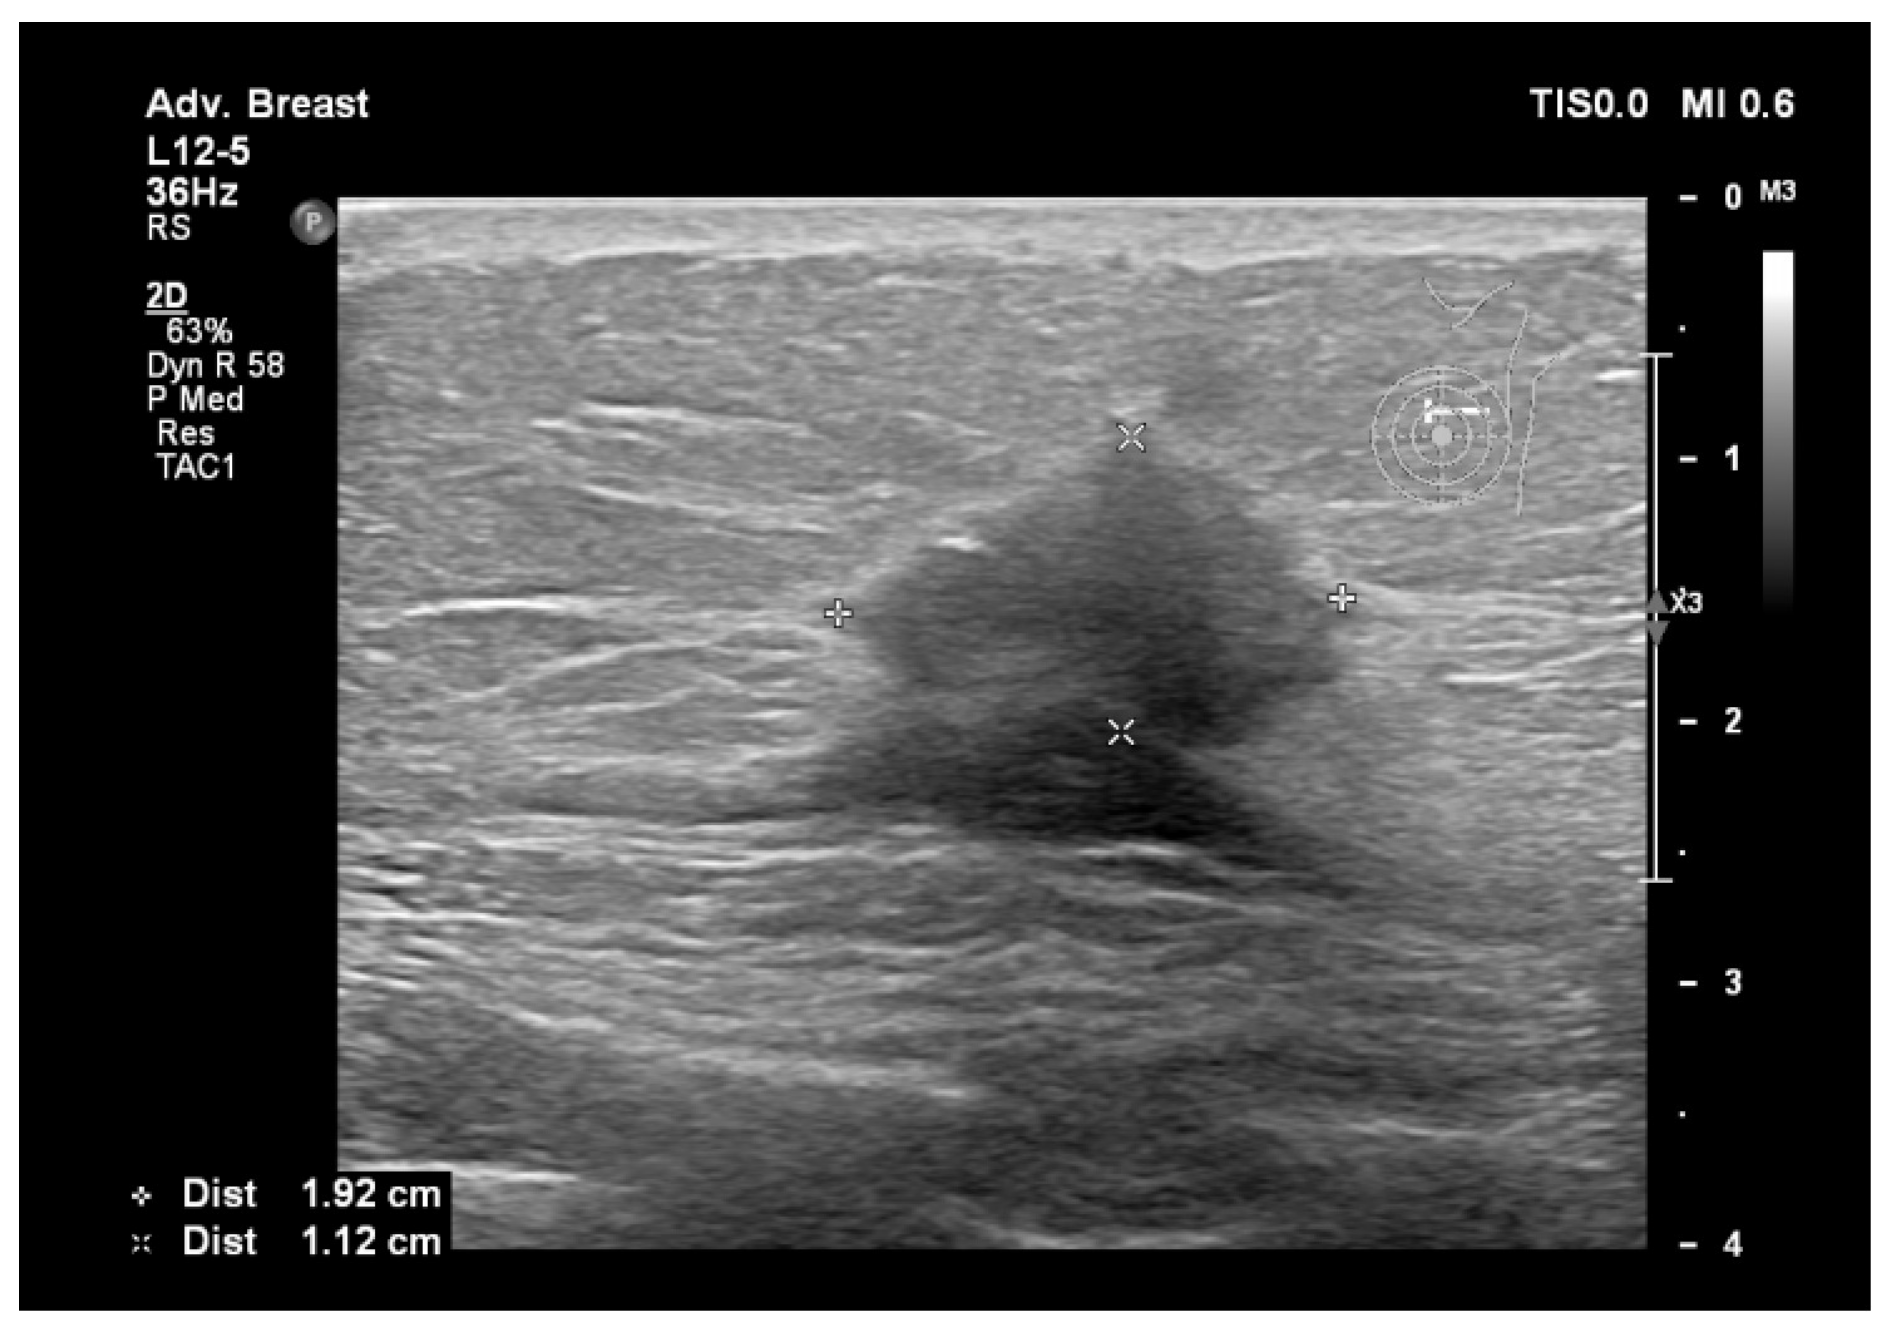

Figure 3.

Breast lesion detected using ultrasound, shows a hypoechogenic solid nodule, with spiculations and ill-defined margins.

Figure 3 and Figure 4, same suspicious lesion seen both on ultrasound and on mammography in the left breast, presenting ill-defined margins and spiculations on both imaging methods.